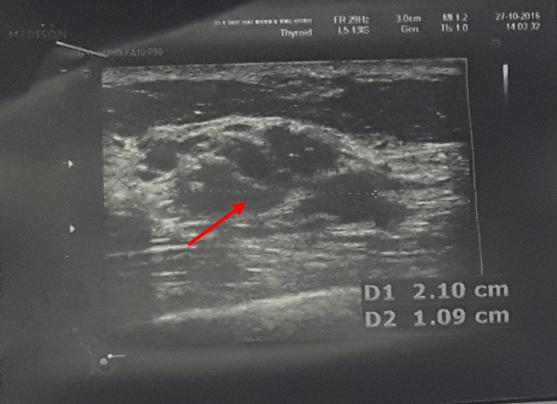

Siêu âm tuyến vú: vị trí ¼ dưới trong vú phải có khối giảm âm, bờ không đều, kích thước khoảng 2,1x1,1cm. Vú trái nhu mô đều, không thấy khối bất thường.

Hình 2: Hình ảnh siêu âm vú: u vú phải ranh giới không rõ trên siêu âm (mũi tên đỏ)